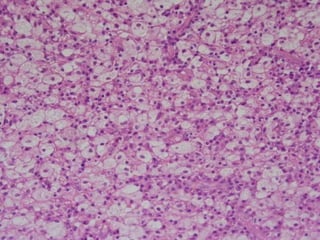

Chronic Pulpitis

 Histopathological

Features:

Mononuclear inflammatory cell

infiltration.

 Evidence of fibroblastic activity.

 Minute abscess if exist it is localized

by granulation tissue.